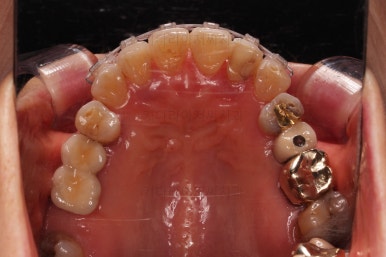

마무리 때의 사진입니다.

교정치료 자체는 9개월만에 끝냈지만 잇몸이 약해서 재발이 우려됐고 예후가 불량해서 뽑아야 되는 치아도 있어 해당 부분을 임플란트를 할 지 최대한 계속 써볼지 등에서 고민하느라 최종 종료는 한참 더 걸리긴 했어요.

부착형 유지장치 뿐만 아니라 보조적으로 재발을 막아줄 목적의 독특한 형태의 뺐다꼈다 유지장치도 드렸어요.(여기서는 공개 안할겁니다. 비밀입니다. ㅎㅎ)

부산부분교정 전후사진을 비교해 볼게요.

치열이 매우 가지런해졌고 보이던 틈새도 다 없어졌으며 뻐드러진 느낌도 완벽히 좋아졌어요.

잇몸에서 쑤욱 빠져나와 보이던 치아도 원위치를 찾았고요.

앞니도 약간이나마 뒤로 들어가서 입매도 많이 좋아졌어요.